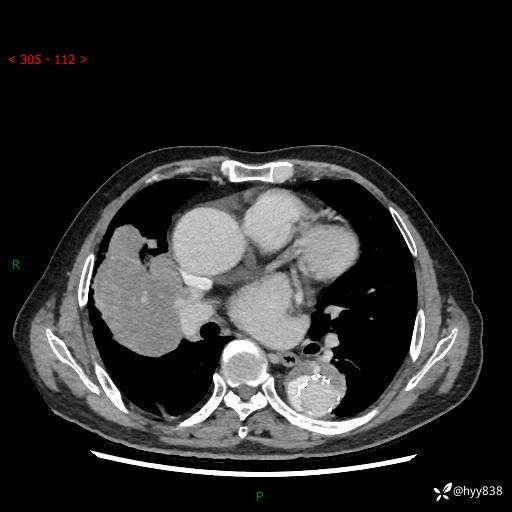

静脉期